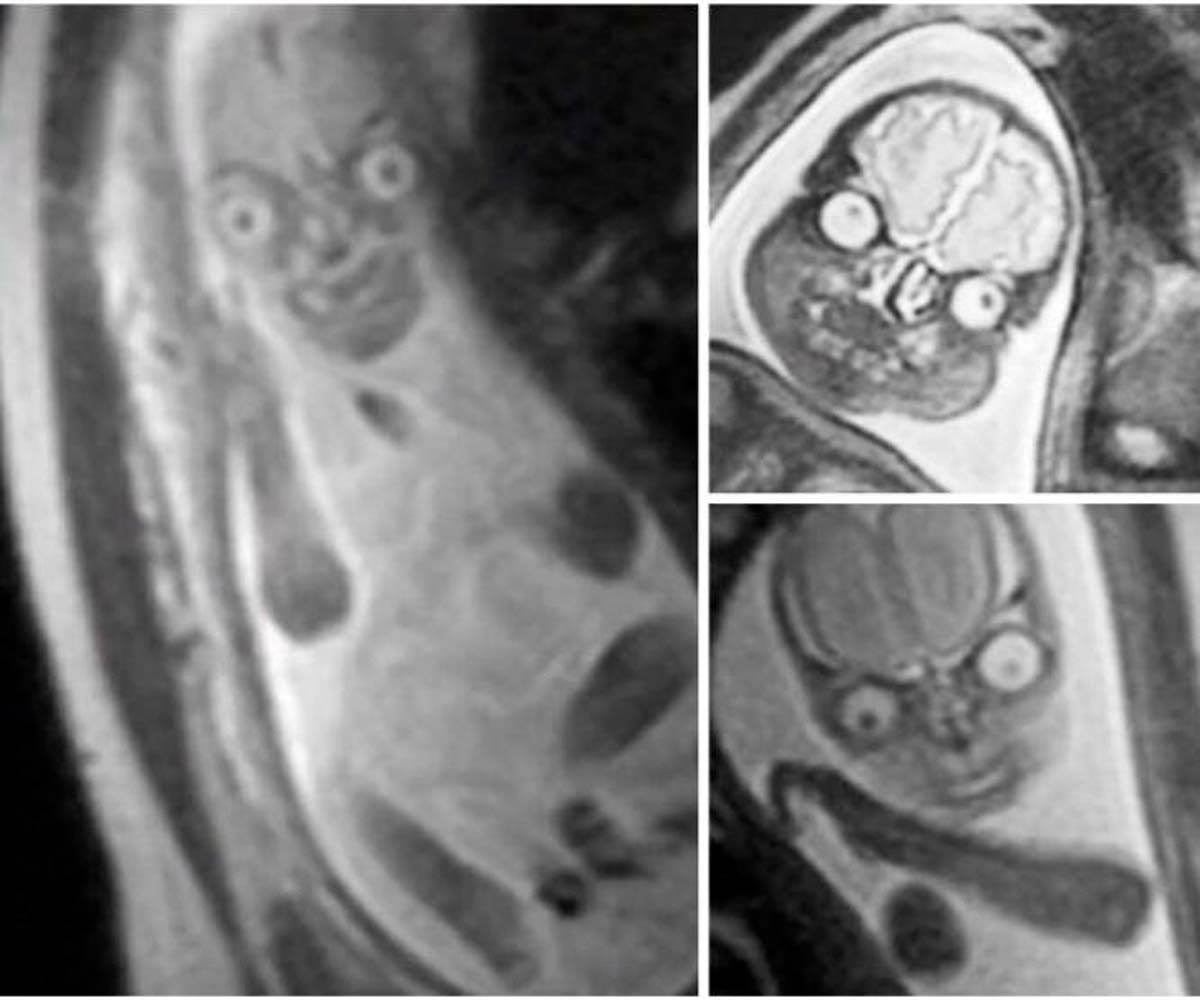

Reddit/printscreen Magnetna rezonanca bebe u stomaku je posebno uznemirila ljude.